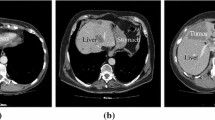

The span of modern medical imaging provides new and efficient techniques for segmentation of liver that are used by the clinicians to view in order to diagnose, monitor and treat liver diseases. Liver cancer is one of the most prominent diseases which cause death. Extraction of liver in different modalities is a difficult task because of its varying shape, similarity between organ intensities and variability in liver region intensities. In this review paper, a study has been carried out on liver segmentation in CT and MRI images with different methodologies and datasets. The observation has been made to highlight the merits, demerits and performance metrics of different works published.